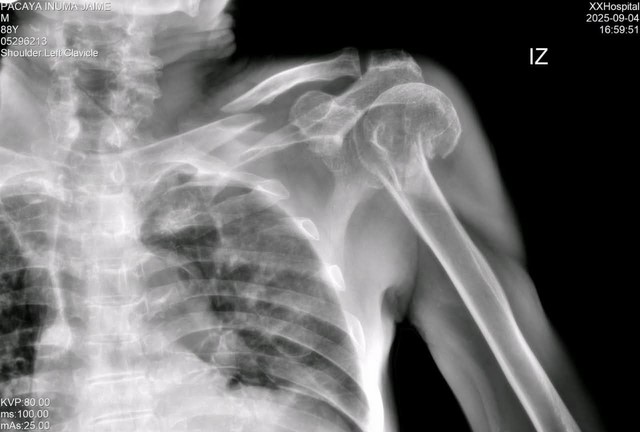

El diagnóstico médico determinó la necesidad de una intervención quirúrgica en la clavícula; sin embargo, pese a la urgencia, el paciente lleva dos semanas internado sin una respuesta clara sobre la fecha de su operación.